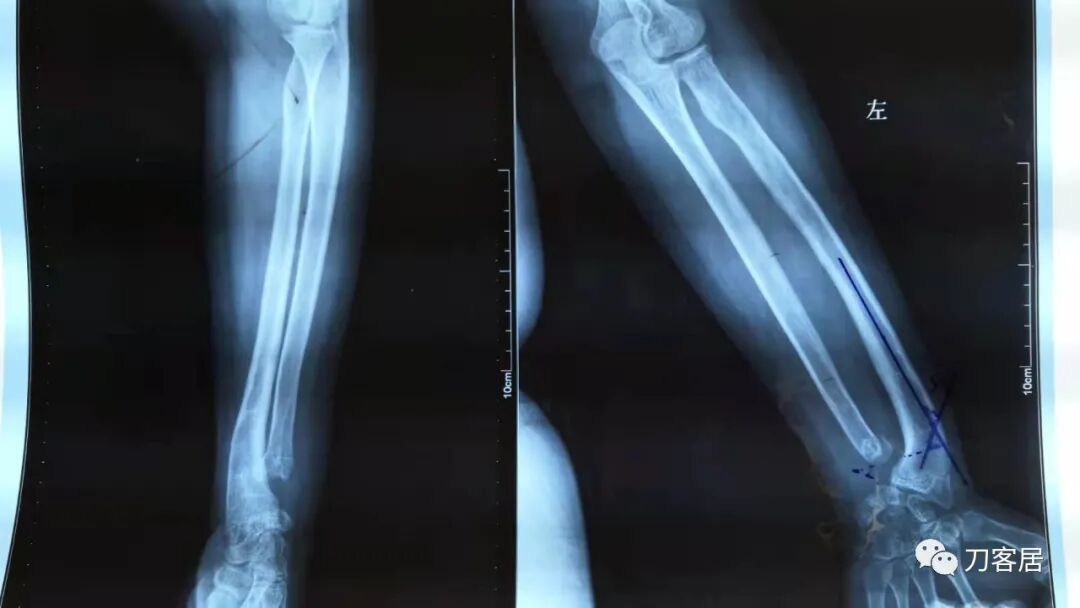

下面是这个6岁孩子,尺桡骨远端双骨折的术前及术后片子和外观照片。

2.  这个骨折处理起来也很简单,单纯的打石膏托或者中医的小夹板,或者正规的包括腕关节和肘关节的管型石膏外固定4周即可治愈该骨折。实在不行,如果这个孩子比较听话,不太调皮的话,用一本书,一个三角巾悬吊固定4周,都可以治愈该骨折。但是给这个患者用外固定架做了手术,而且桡骨远端的几颗克氏针距离骨折线太近,其中一枚克氏针进入到骨折间隙内。从这个术中图片来看,术者的外固定手术技术也有待于进一步的提高。毕竟术者应该还很年轻。从X线片来看,前臂及手的尺侧有不透光影,应该还使用了外固定石膏绷带托,而且我猜测应该是高分子的石膏绷带托,这个是纯属猜测,不一定是对的,不过如何解释前臂尺侧的不透光影呢?如果真是用了石膏绷带外固定的话,那为啥要做手术呢?外固定架术后就不该再用石膏绷带托辅助了。